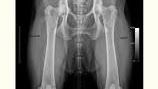

La dysplasie des hanches, fréquente chez les Bergers Australiens, peut entraîner une boiterie et une raideur articulaire. Pour prévenir cette condition,...